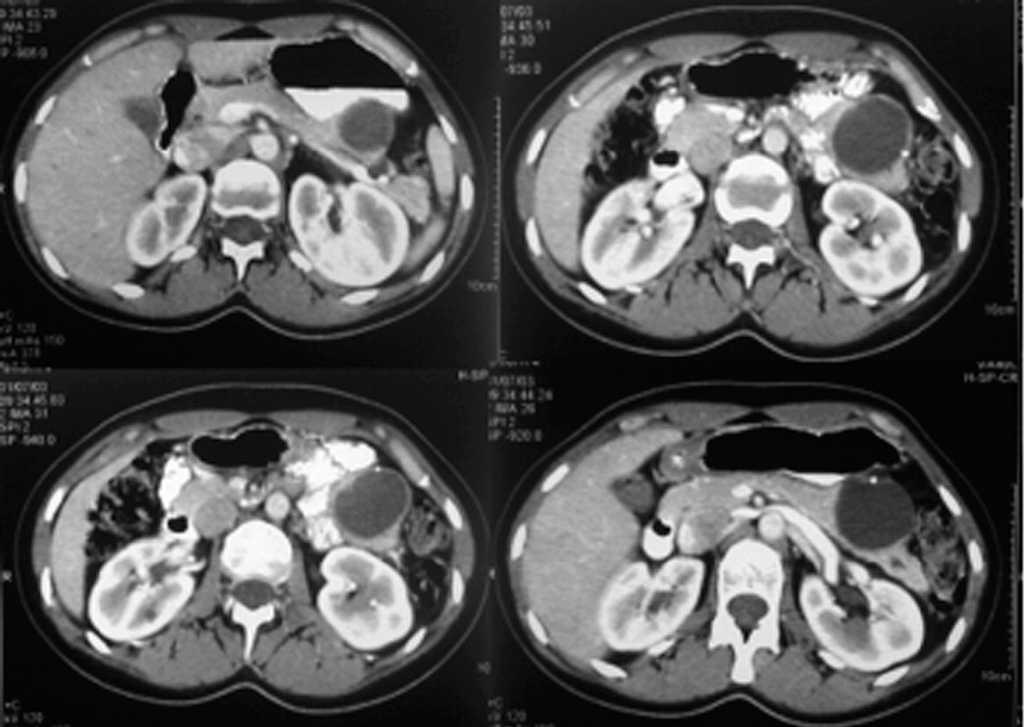

Mujer de 28 años, sin antecedentes personales o familiares de interés, que consulta por molestias inespecíficas en el hipocondrio izquierdo (HCI) sin otra sintomatología acompañante. La exploración física, salvo por la presencia de discretas molestias en la palpación profunda del HCI, es completamente normal. Se efectuó una ecografía abdominal que reveló la presencia de una masa quística en cuerpo/cola de páncreas de carácter unilocular. Ante estos hallazgos se efectuó una tomografía computarizada (TC) que evidencia masa quística unilocular de 6 x 6 cm localizada en la cola pancreática con calcificaciones periféricas (fig. 1). Con la sospecha de neoplasia mucinosa o tumor sólido seudopapilar, la paciente fue intervenida quirúrgicamente practicándose una pancreatectomía corporocaudal (fig. 2). La evolución postoperatoria fue satisfactoria. El estudio anatomopatológico de la pieza quirúrgica reveló que se trataba de un cistoadenoma seroso unilocular macroquístico (fig. 3).

Fig. 1. Hallazgos en la tomografía computarizada. Se aprecia una lesión quística localizada en cuerpo/cola de páncreas, de unos 6 x 6 cm, no tabicada, sin calcificaciones, en ausencia de metástasis o adenopatías.